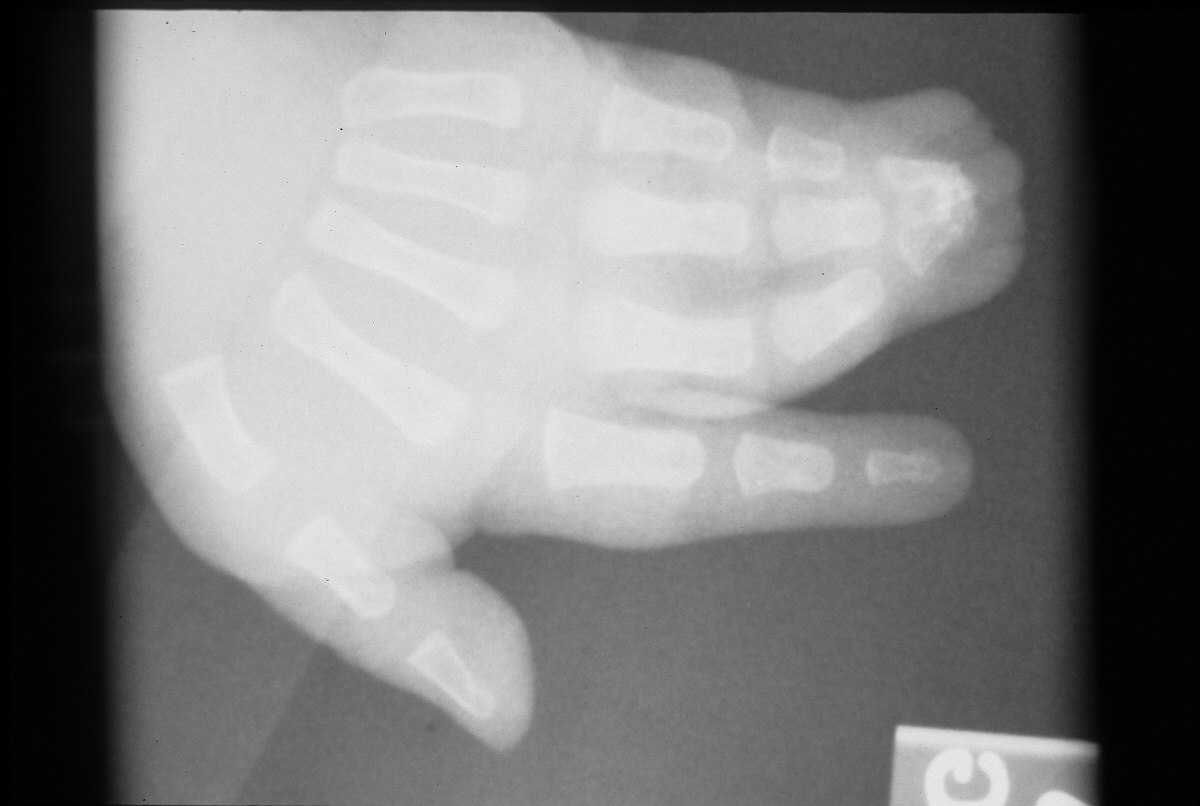

Bilateral middle, ring and small acrosyndactyly.

All procedures were bilateral at the same setting, but are illustrated here only on the right side.

First stage: fingertip separation and surfacing with hypothenar skin grafts. This converts the syndactyly from complex to simple and buys some time for growth by lessening the deforming forces of the terminal bony syndactyly.